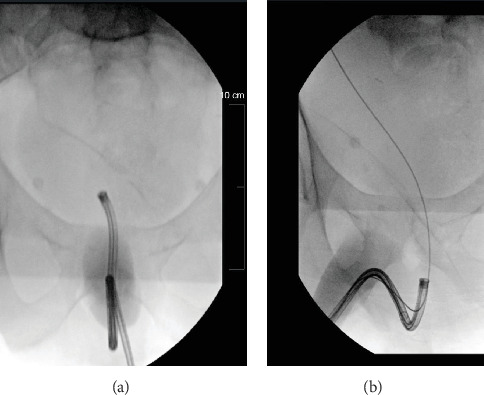

Abdominoplasty is a frequently performed elective procedure, often indicated for patients after substantial weight loss resulting in significant redundant skin. Closing techniques and the lifting of the mons pubis during abdominoplasty have been proposed to alleviate symptoms of stress urinary incontinence by elevating and supporting the urethra. Despite these observations, the impact of abdominoplasty on pelvic anatomy and subsequent endoscopic procedures remains underexplored and underreported. We present a case where cystoscope passage as part of endoscopic laser lithotripsy for nephrolithiasis was impeded by altered anatomy in a patient with a history of Fleur-de-Lis abdominoplasty.